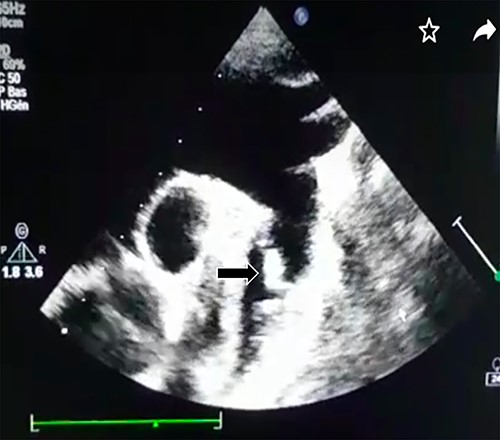

Transthoracic echocardiography revealed a large PDA (10 mm) with left-to-right shunt and a fixed structure on the wall of the pulmonary artery, with erratic movement indicative of a vegetation (Fig. 1), and mobile vegetation attached to the wall of the descending aorta in the supra-sternal view (Fig. 2) and a left ventricle with conserved systolic function and 55-mm end-diastolic diameter.

Large PDA and a fixed structure on the wall of the pulmonary artery.

Supra-sternal view: vegetation attached to the wall of the descending aorta.